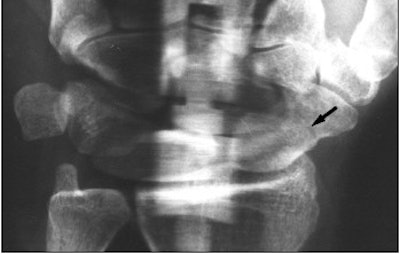

![]() ![]() |

| Forty-nine-year old woman with acute trauma of the wrist. Conventional radiography and panoramic radiography were performed two weeks after injury. Conventional radiographs (above) show no evidence of fracture. |